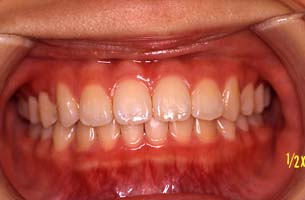

正面 | 矯正前 |

| 120日目 |

| 矯正後(約一年半後) |

平成15年から現在までで定岡先生の治療により無事犬歯も中に入り,とても綺麗な歯並びとなり,正直驚きました。

矯正治療を始めて約3ヶ月後に歯並びがよくなってきたのを見て,安心されていた様でした。

治療後,このお子様はもとよりお母様にも大変感謝され,私共も大変嬉しかったケースでした。